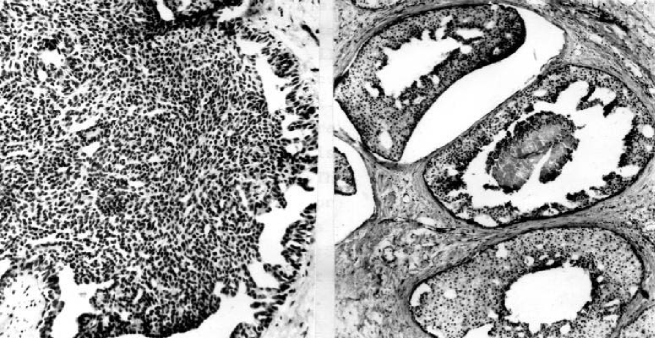

The introduction of the parameters was motivated by the fact that tumor cell shape (see Figures 6 and 7) represents a visual manifestation of an underlying balance of forces and chemical reactions [32]. Specifically, the parameters represent the following quantities:

The ability to estimate the growth pattern of an individual tumor cell type on the basis of morphological measurements should have general applicability in cellular investigations, cell–growth kinetics, cell transformation and morphogenesis [34].

Cell spreading alone is conducive to proliferation and increases in DNA synthesis, indicating that cell morphology is a critical determinant of cell function, at least in the presence of optimal growth factors and extracellular matrix (ECM) binding [35]. In many cells, the changes in morphology can stimulate cell proliferation through integrin-mediated signaling, indicating that cell shape may govern how individual cells will respond to chemical signals [36].

The proposed model (20)–(23) describes chaotic behavior relevant to the invasion of cancer cells (see Figures 5 and 6). As devices for controlling metastasis/chaos we suggest the following processes: Cellular retraining of cancer stem cells and/or activation of positive function of cyclin-dependent kinase inhibitor p27 and/or decreased expression of SATB1, which is correlated with aggressive tumor phenotype in breast cancer and shorter patient survival time [27, 29, 30, 31].

The authors are grateful to Professor Nada Sljapic, MD, PhD, from the Medical School, University of Novi Sad, for expert advice and breast cancer slides.